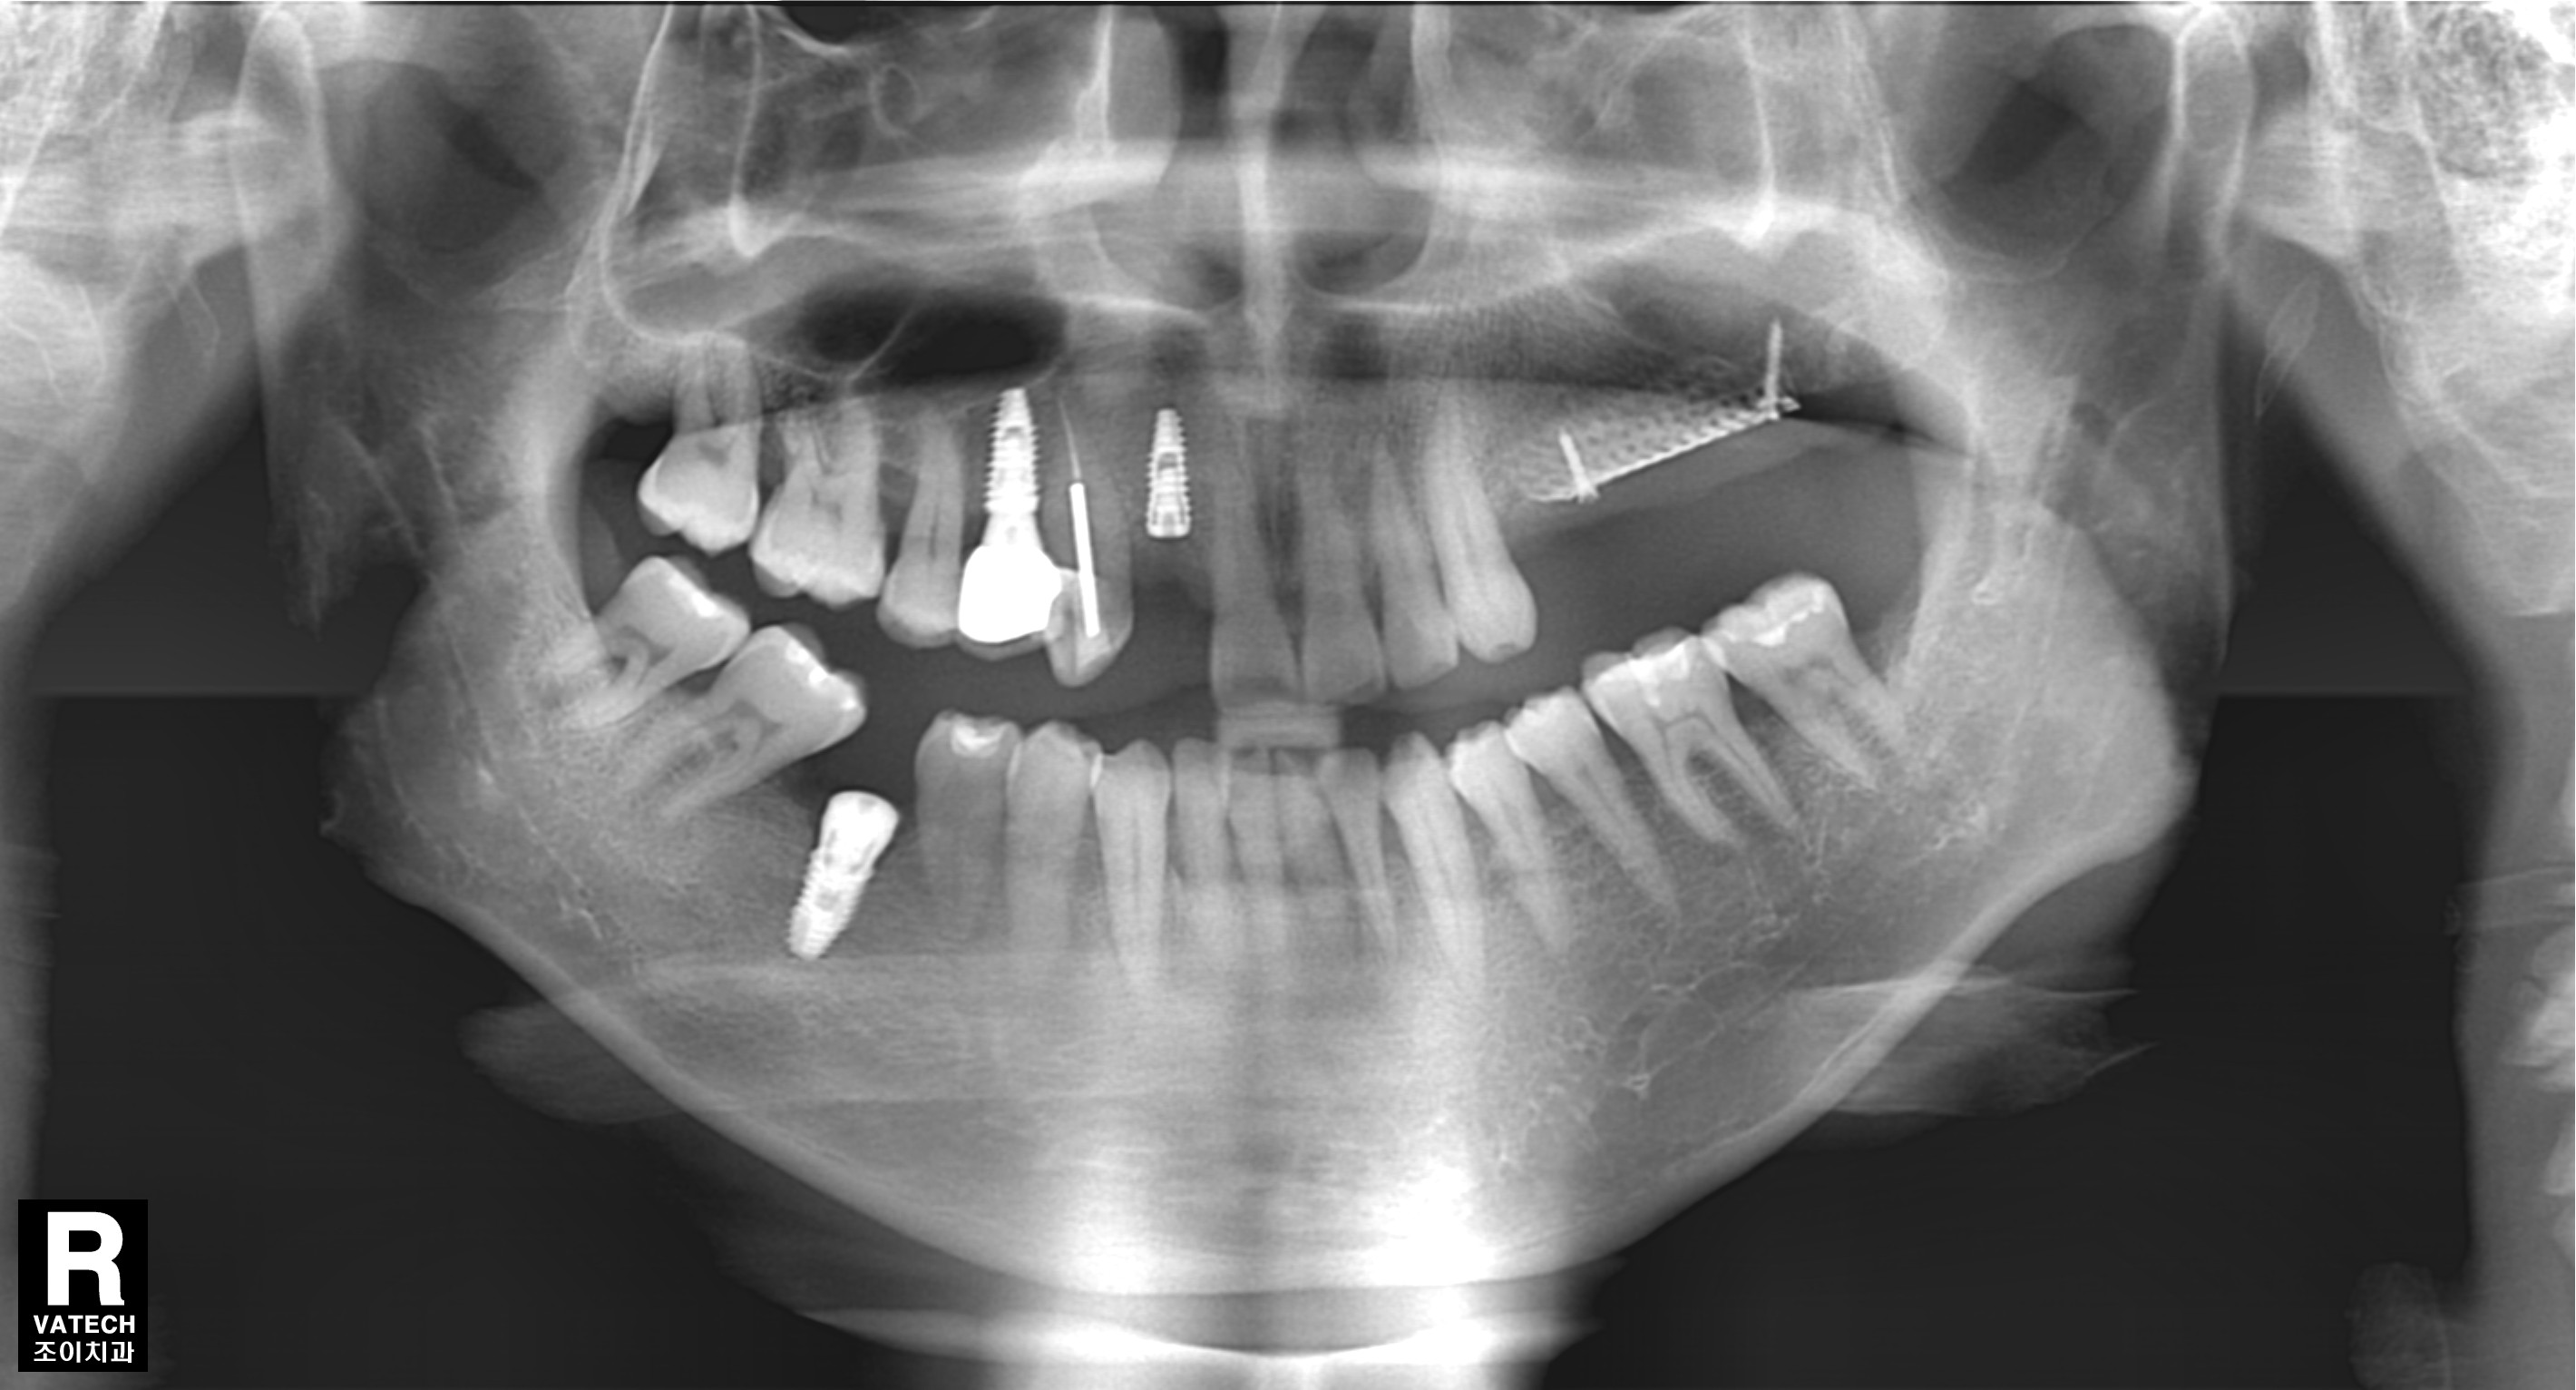

[임플란트] 제목 : 골이식

올바른 임플란트 식립의 초석은 충분한 뼈.